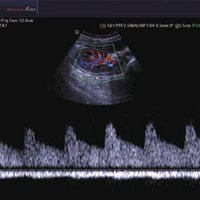

• Farb-Doppler

• Pulsed Wave (PW)-Spektral-Doppler

• Continuous Wave (CW)-Doppler

• Power-Doppler (PD)

• Directional Power Doppler (DPD)